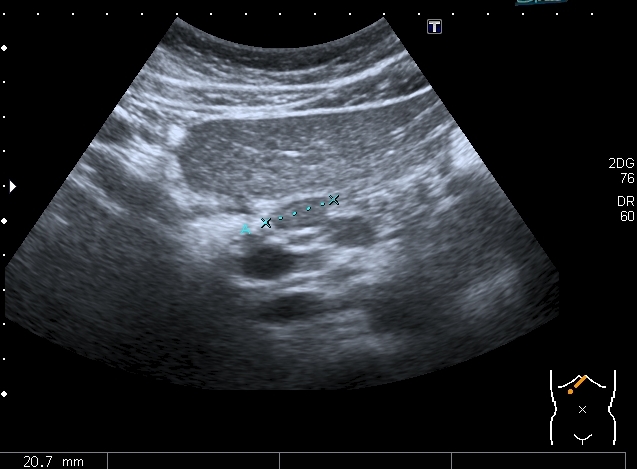

Девочка 13 лет, в течение 2-х недель температура до 38, СОЭ - 40 мм\ч, СРБ - 30.

На УЗИ: Учитывая клинику, лабораторные данные поставил гистиоцитарную инфильтрацию печени и селезёнки при генерализованной инфекции. Несколько раз встречался со схожими случаями, на фоне антибиотикотерапии изменения уходили. Но в данном случае девочка уже получала антибиотики в течение недели, на этом фоне не получено ни клинического , ни лабораторного улучшения, а на УЗИ очаги стали больше. Нужно ли расширять дифференциально -диагностический ряд? Ваши мнения

Имхо, по УЗ-семиотике - множественные небольшие абсцессы.

Из -за того , как назвать данные изменения у нас в больнице постоянно возникают споры между педиатрами и хирургами, а крайние - мы. Если мы в своём заключении упомянём слово "абсцесс" - девочку сразу же переведут в хирургическое отделение: абсцесс= гной, где гной - там разрез. Весь вопрос в том , что гноя в этих очагах нет и хирурги категорически отказываются участвовать в лечении данного заболевания, скорее это инфильтраты, или по лекции С. И. Пиманова - гистиоцитоз печени и селезёнки. Упомянув данное слово , мы ввергаем педиатров в панику, т. к. у них возникает ассоциация с гистиоцитозом X, хотя это несолько из другой оперы.KapustinSV писал(а):Имхо, по УЗ-семиотике - множественные небольшие абсцессы.

Есть мысль о КТ с контрастированием , думаю в данных очагах накопление контраста должно отличаться от очаговых поражениях при лимфомах.